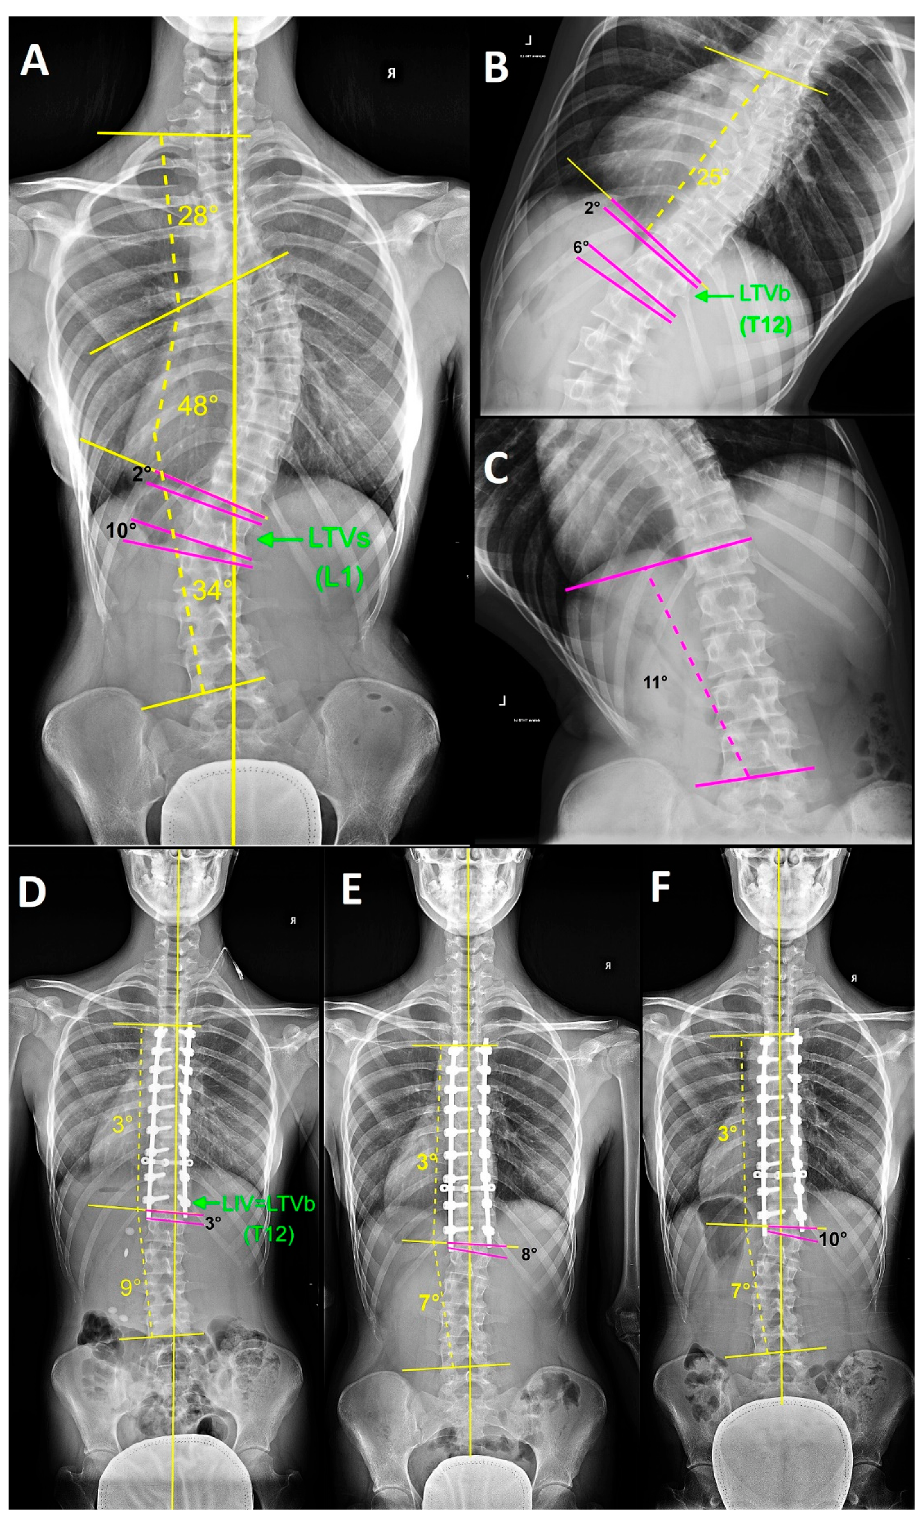

From www.mdpi.com

Symmetry Free FullText The Role of Bending Films in the Lowest Bending Lumbar X Rays The entire lumbar spine should be visible, with demonstration of t11/t12 superiorly and the sacrum inferiorly. Scoliosis is defined as a lateral curvature of the spine in the coronal plane. The most common causes include idiopathic. The lumbar spine is made up of five vertebral bones. No patient rotation as evident by central spinous. The functional examination of the lumbar. Bending Lumbar X Rays.

From www.researchgate.net

Preoperative posteroanterior fulcrumbending xray of thoracic spine Bending Lumbar X Rays Begin by confirming the patient’s details, reviewing the. The entire lumbar spine should be visible, with demonstration of t11/t12 superiorly and the sacrum inferiorly. The most common causes include idiopathic. The aim of this view is to assess patients' lateral range of spinal motion 1 in the vertebral column as part of a scoliosis series. Scoliosis is defined as a. Bending Lumbar X Rays.